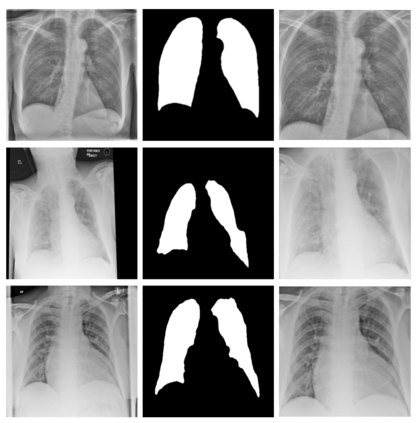

During the COVID-19 pandemic, the sheer volume of imaging performed in an emergency setting for COVID-19 diagnosis has resulted in a wide variability of clinical CXR acquisitions. This variation is seen in the CXR projections used, image annotations added and in the inspiratory effort and degree of rotation of clinical images. The image analysis community has attempted to ease the burden on overstretched radiology departments during the pandemic by developing automated COVID-19 diagnostic algorithms, the input for which has been CXR imaging. Large publicly available CXR datasets have been leveraged to improve deep learning algorithms for COVID-19 diagnosis. Yet the variable quality of clinically-acquired CXRs within publicly available datasets could have a profound effect on algorithm performance. COVID-19 diagnosis may be inferred by an algorithm from non-anatomical features on an image such as image labels. These imaging shortcuts may be dataset-specific and limit the generalisability of AI systems. Understanding and correcting key potential biases in CXR images is therefore an essential first step prior to CXR image analysis. In this study, we propose a simple and effective step-wise approach to pre-processing a COVID-19 chest X-ray dataset to remove undesired biases. We perform ablation studies to show the impact of each individual step. The results suggest that using our proposed pipeline could increase accuracy of the baseline COVID-19 detection algorithm by up to 13%.